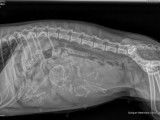

UliannaQuentin et Ulianna - Quentin est un bel étalon qui vie en ItalieRadiographie des chiots